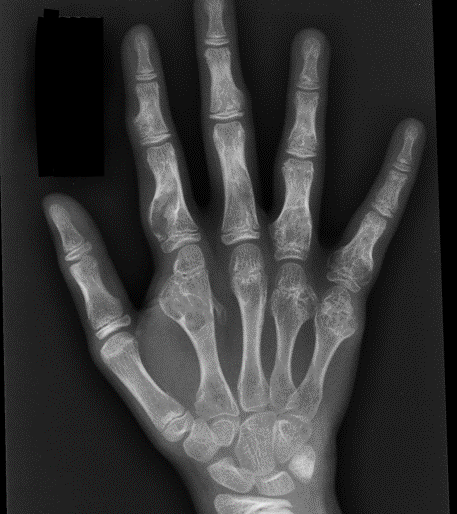

Hands > feet

Hand & Feet

Often present in first decade of life with palpable masses on hands and feet

- cosmetic issues / stiffness / pathological fractures

Klein et al J Hand Surg Am 2018

- 10 pediatric patients with metacarpal or phalangeal enchondromas

- curettage and corticoplasty (trimming of excess bone) for hand enchondromas

- improved range of motion and cosmesis